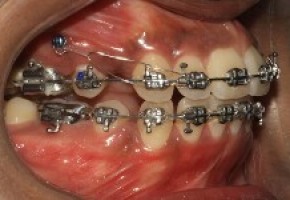

Traditional metal braces are the most common type of braces and are more comfortable today than ever before. Made of high-grade stainless steel, metal braces straighten your teeth using metal brackets and archwires. With metal braces, you have the option of adding colored elastics (rubber bands) for a more unique and colorful smile.